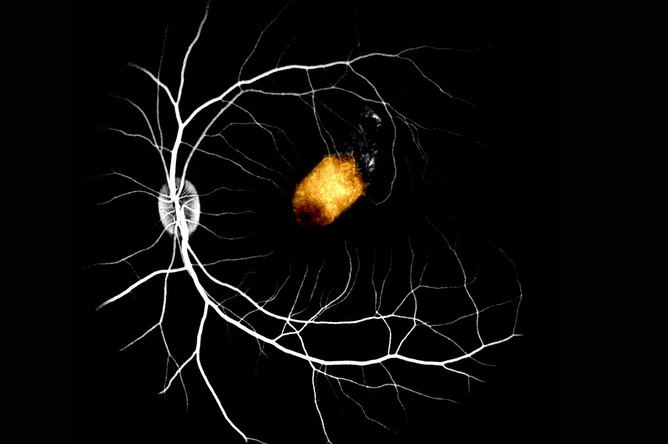

Глаза мертвеца: найден новый способ лечения слепоты

Ученые придумали, как лечить слепоту с помощью глаз трупов